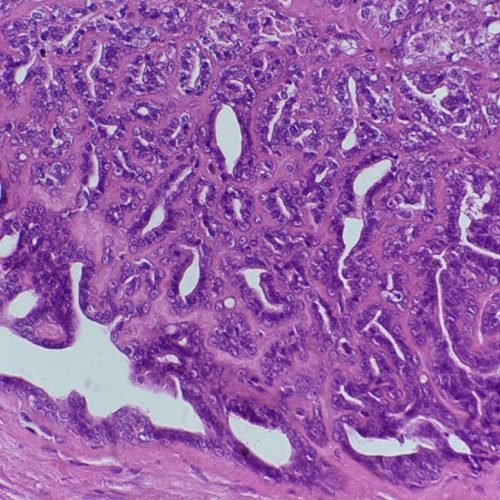

A histopatologia é o exame microscópico de tecidos biológicos para o diagnóstico de doenças, sendo o diagnóstico definitivo (“padrão ouro”) para a maioria dos processos.

O exame histopatológico envolve o exame de uma biópsia (ou seja, uma amostra retirada cirurgicamente por um médico veterinário) e analisado por um médico veterinário especializado, chamado patologista.